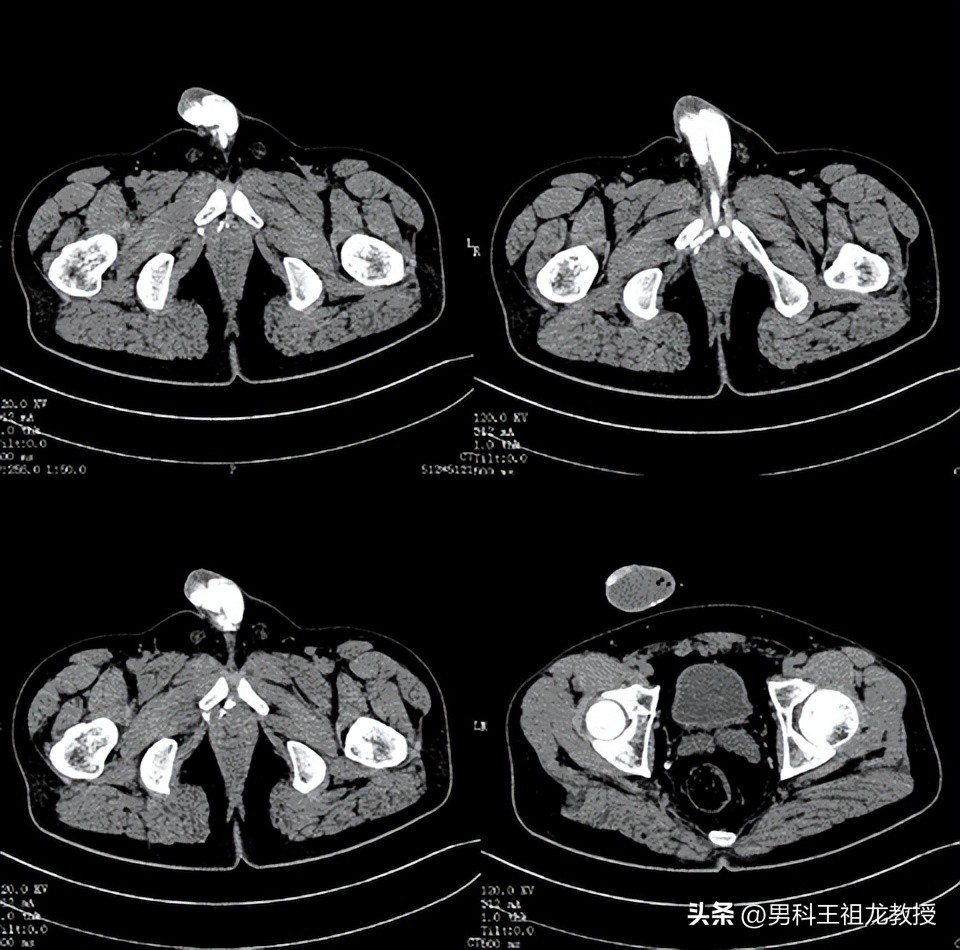

造影剂增强计算机断层扫面成像

我院男科,完成首例CT下阴茎海绵体造影及三维血管重建手术!

王祖龙主任仔细阅片后,告知患者其明确诊断为 静脉性勃起功能障碍 ,在阴茎背深静脉及阴茎右侧海绵体脚静脉存在两处静脉漏,建议患者择期手术治疗